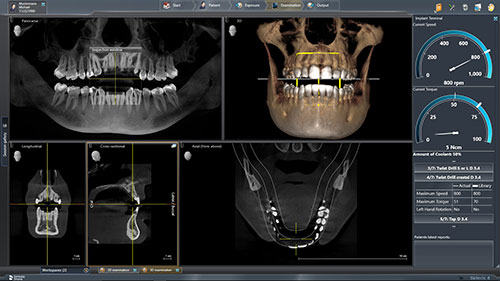

Dentsply Sirona’s integrated solutions for implant dentistry enable dental professionals to deliver safer and more efficient treatment processes as well as increased comfort and improved quality of life for their patients. The merger between DENTSPLY and Sirona has brought together two companies with long-term expertise in their respective fields, providing innovative and clinically tested technology, … Read more